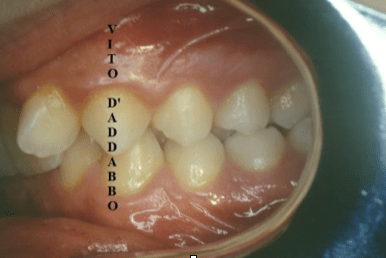

Si parla di morso profondo quando i denti anteriori superiori coprono per più di un terzo quelli inferiori.

Se molto profondo, nel corso degli anni, può provocare danni parodontali ai tessuti di sostegno del dente (gengiva, legamento alveolo-dentale, osso alveolare). Nell’esempio riportato è presente una malocclusione di II classe seconda divisione.